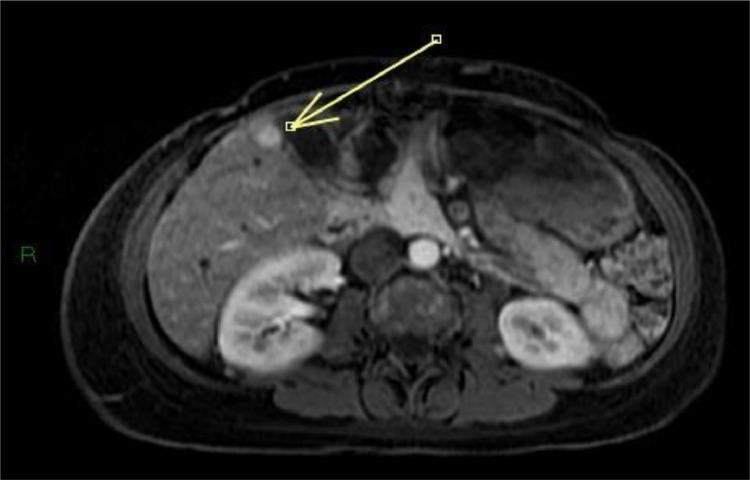

Pregnancy-associated breast cancer (PABC) presents unique challenges. This type of breast cancer is often more aggressive than that diagnosed in nonpregnant women, and its diagnosis is frequently delayed. Several factors contribute to this delay, including the physiological changes that occur during pregnancy, such as breast enlargement, breast tenderness and increased tissue density, which can mask early signs of malignancy. Additionally, a lack of awareness among healthcare providers can lead to symptoms being dismissed as normal pregnancy-related changes, and then being underestimated. Consequently, PABC is often diagnosed at more advanced stages, which can result in a poorer prognosis for the patient. This case study reports a 36-year-old woman in good general health, who received histological diagnosis of breast cancer during her pregnancy after presenting for self-detection of an enormous palpable breast mass. Prior to hospitalization, the patient had been treated with antibiotics in the mistaken belief that it was infectious mastitis; subsequently, considering the huge dimensions of the mass and the presence of lymph node metastases, neoadjuvant chemotherapy was started until induction of labor. Imaging techniques such as ultrasonography (and mammography as an adjunct) and nonenhanced MRI (due to potential toxicity of gadolinium to the fetus) can be used for staging maternal breast disease during pregnancy. A multidisciplinary approach which involves the radiologist, the breast surgeon, the oncologist and the gynecologist is fundamental to ensure the best prognostic outcomes for both the mother and the fetus.

妊娠相关乳腺癌(PABC)带来了独特的挑战。这种类型的乳腺癌往往比非妊娠女性所诊断出的乳腺癌更具侵袭性,而且其诊断常常被延迟。有几个因素导致了这种延迟,包括怀孕期间发生的生理变化,如乳房增大、乳房压痛和组织密度增加,这些变化可能掩盖恶性肿瘤的早期迹象。此外,医疗保健提供者缺乏认识可能导致症状被视为正常的妊娠相关变化而被忽视,进而被低估。因此,PABC往往在更晚期才被诊断出来,这可能导致患者预后较差。本病例报告了一名36岁总体健康状况良好的女性,她在怀孕期间自行发现一个可触及的巨大乳房肿块后接受了乳腺癌的组织学诊断。在住院之前,患者因误以为是感染性乳腺炎而接受了抗生素治疗;随后,考虑到肿块巨大且存在淋巴结转移,开始进行新辅助化疗直至引产。超声检查(以及作为辅助手段的乳腺X线摄影)和非增强MRI(由于钆对胎儿可能存在毒性)等成像技术可用于在怀孕期间对母体乳腺疾病进行分期。涉及放射科医生、乳腺外科医生、肿瘤内科医生和妇科医生的多学科方法对于确保母亲和胎儿获得最佳预后结果至关重要。